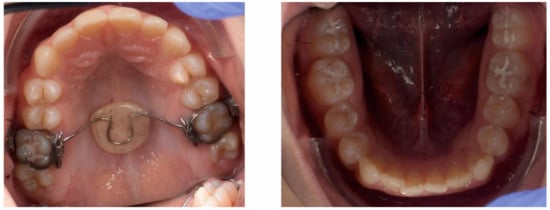

2.3.1. First Treatment Phase—2016—TMJ Splint Therapy

2.3.2. Second Phase of Treatment—2017—Bite-Blocks and Transpalatal Arch